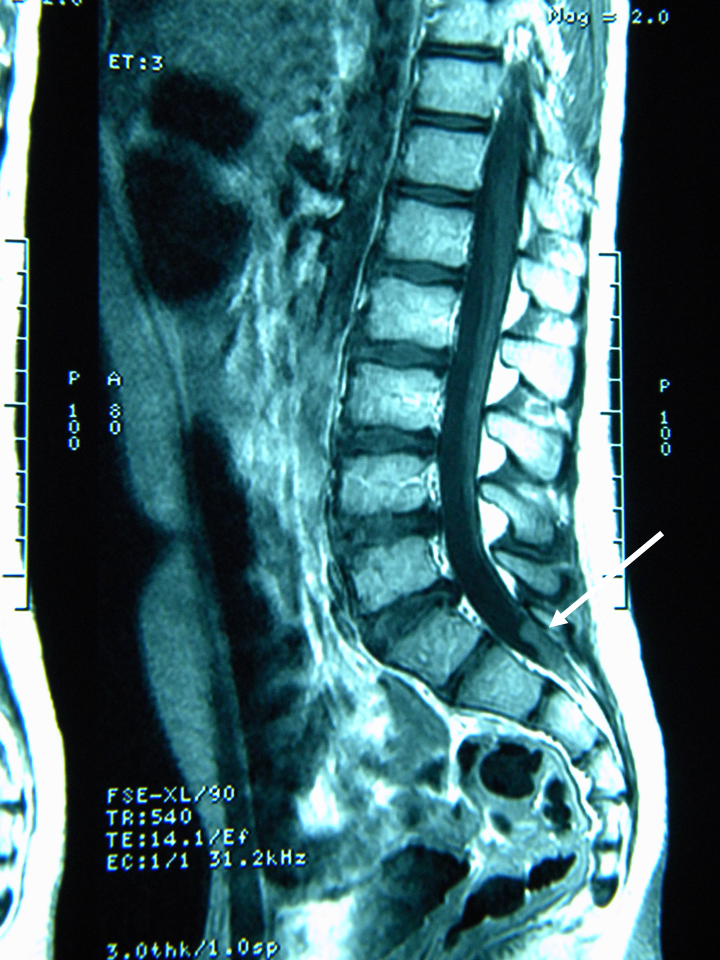

A fine maggio L. viene quindi ricoverato presso il nostro centro per vomito persistente e calo ponderale. L. ha 13 anni e 10 mesi e pesa 39,5 kg (< 10�); la madre riferisce un calo ponderale di circa 13 kg in 4 mesi. Vengono inizialmente formulate alcune ipotesi diagnostiche: RGE, esofagite eosinofila, gastrite Helicobacter pylori-positiva. L. viene sottoposto a una serie di esami di laboratorio e strumentali: le uniche alterazioni riscontrate sono rappresentate da una eosinofilia relativa, da un aumentato livello sierico di IgE e da una positivit� degli skin prick test per pollini di paritaria, acari della polvere e della farina, epitelio di cane e gatto; alla valutazione cardiologica viene rilevata una frequenza cardiaca di 65 bpm. Si decide di eseguire a una nuova EGDS che mostra reperti compatibili con esofagite da reflusso, antrite e reflusso duodenogastrico. Nel sospetto di una ulteriore componente psicogena o neurologica del vomito viene richiesta una valutazione neuropsichiatria infantile che rileva una spiccata deflessione del tono dell�umore necessitante di terapia con valproato, consiglia l�esecuzione di un ulteriore valutazione del fundus oculi e l�esecuzione di RM cerebrale. Il fundus oculi, eseguito nella stessa giornata, non mostra alterazioni patologiche. Alla RM viene evidenziata una neoplasia cerebellare mediana a livello del IV ventricolo (Figura 1 e Figura 2), con iniziale discesa delle tonsille cerebellari nel forame magno e sistema ventricolare sovratentoriale moderatamente dilatato con lievi segni di tensione liquorale; viene eseguita anche una scansione del rachide che evidenzia nodulazioni a livello del sacco durale di L5-S1-S2 da verosimile localizzazione secondaria per diffusione liquorale della neoformazione (Figura 3).

Figura 3. Scansioni di risonanza magnetica del rachide: nodulazioni del sacco durale a livello di L5-S1-S2.